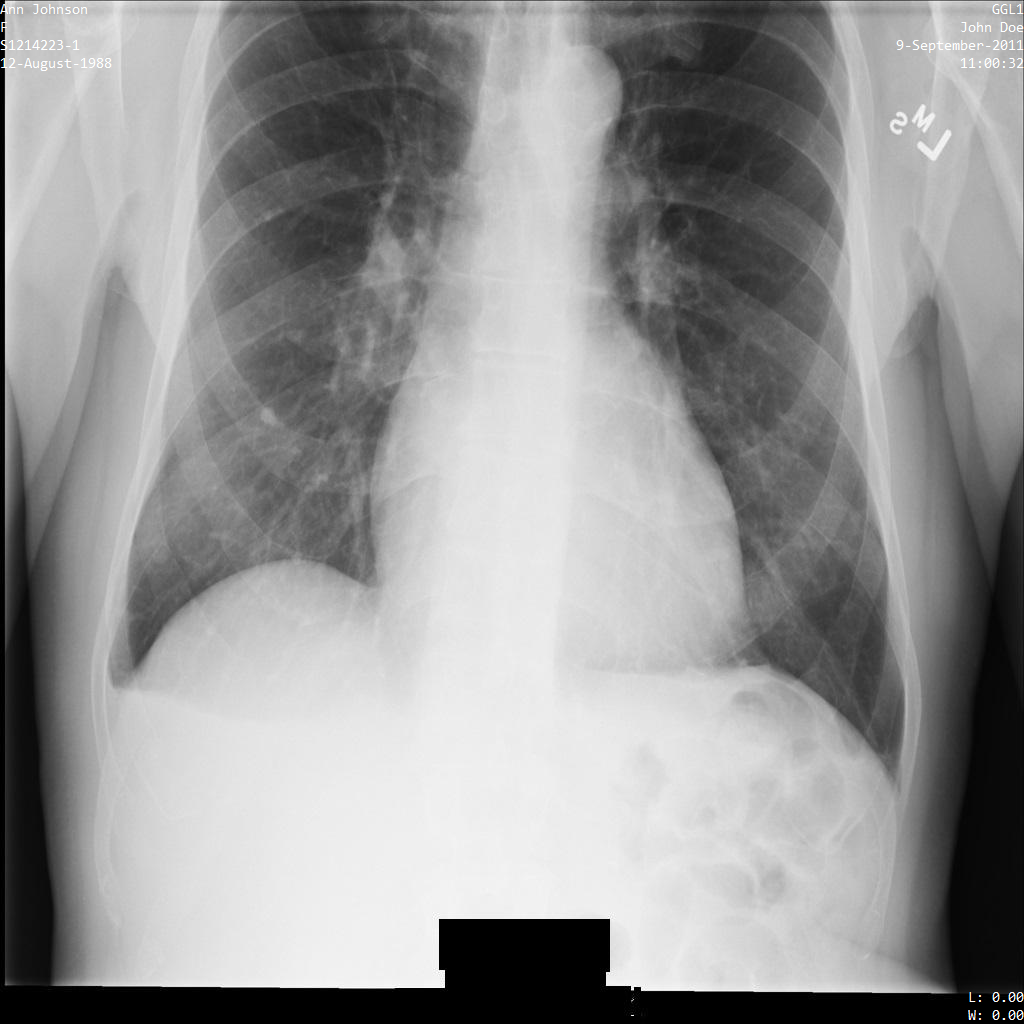

En cada una de las siguientes secciones se proporcionan ejemplos de cómo desidentificar datos DICOM mediante varios métodos. Con cada muestra se proporciona una salida de la imagen anonimizada. En cada ejemplo se usa la siguiente imagen original como entrada:

Puedes comparar la imagen de salida de cada operación de anonimización con la imagen original para ver los efectos de la operación.

Después de enviar la imagen a la API Cloud Healthcare, la imagen aparece de la siguiente manera. Aunque se han ocultado los metadatos que aparecen en las esquinas superiores de la imagen, la información médica protegida (PHI) que aparece en la parte inferior de la imagen no se ha modificado. Para quitar el texto insertado, consulta Ocultar el texto insertado de las imágenes.

REST